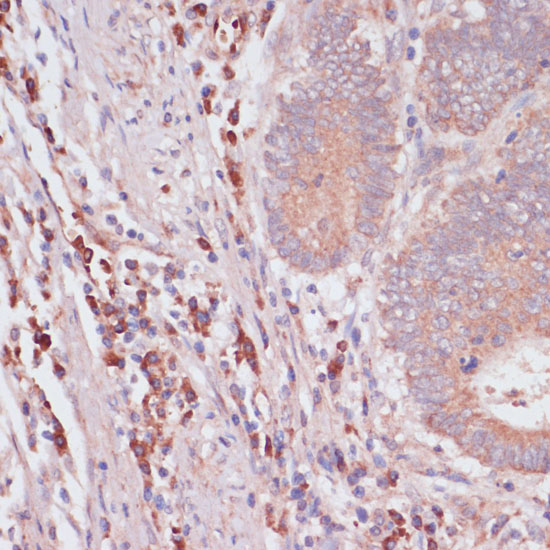

Immunohistochemistry of paraffin-embedded human colon carcinoma using IFNAR2 antibody at dilution of 1:100 (40x lens).